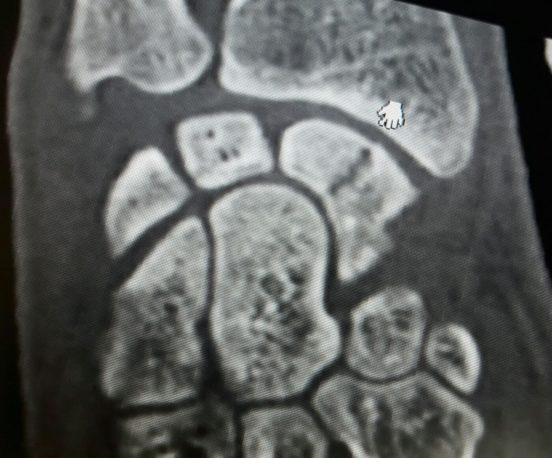

TAC de fractura de escafoides. Posición anteroposterior